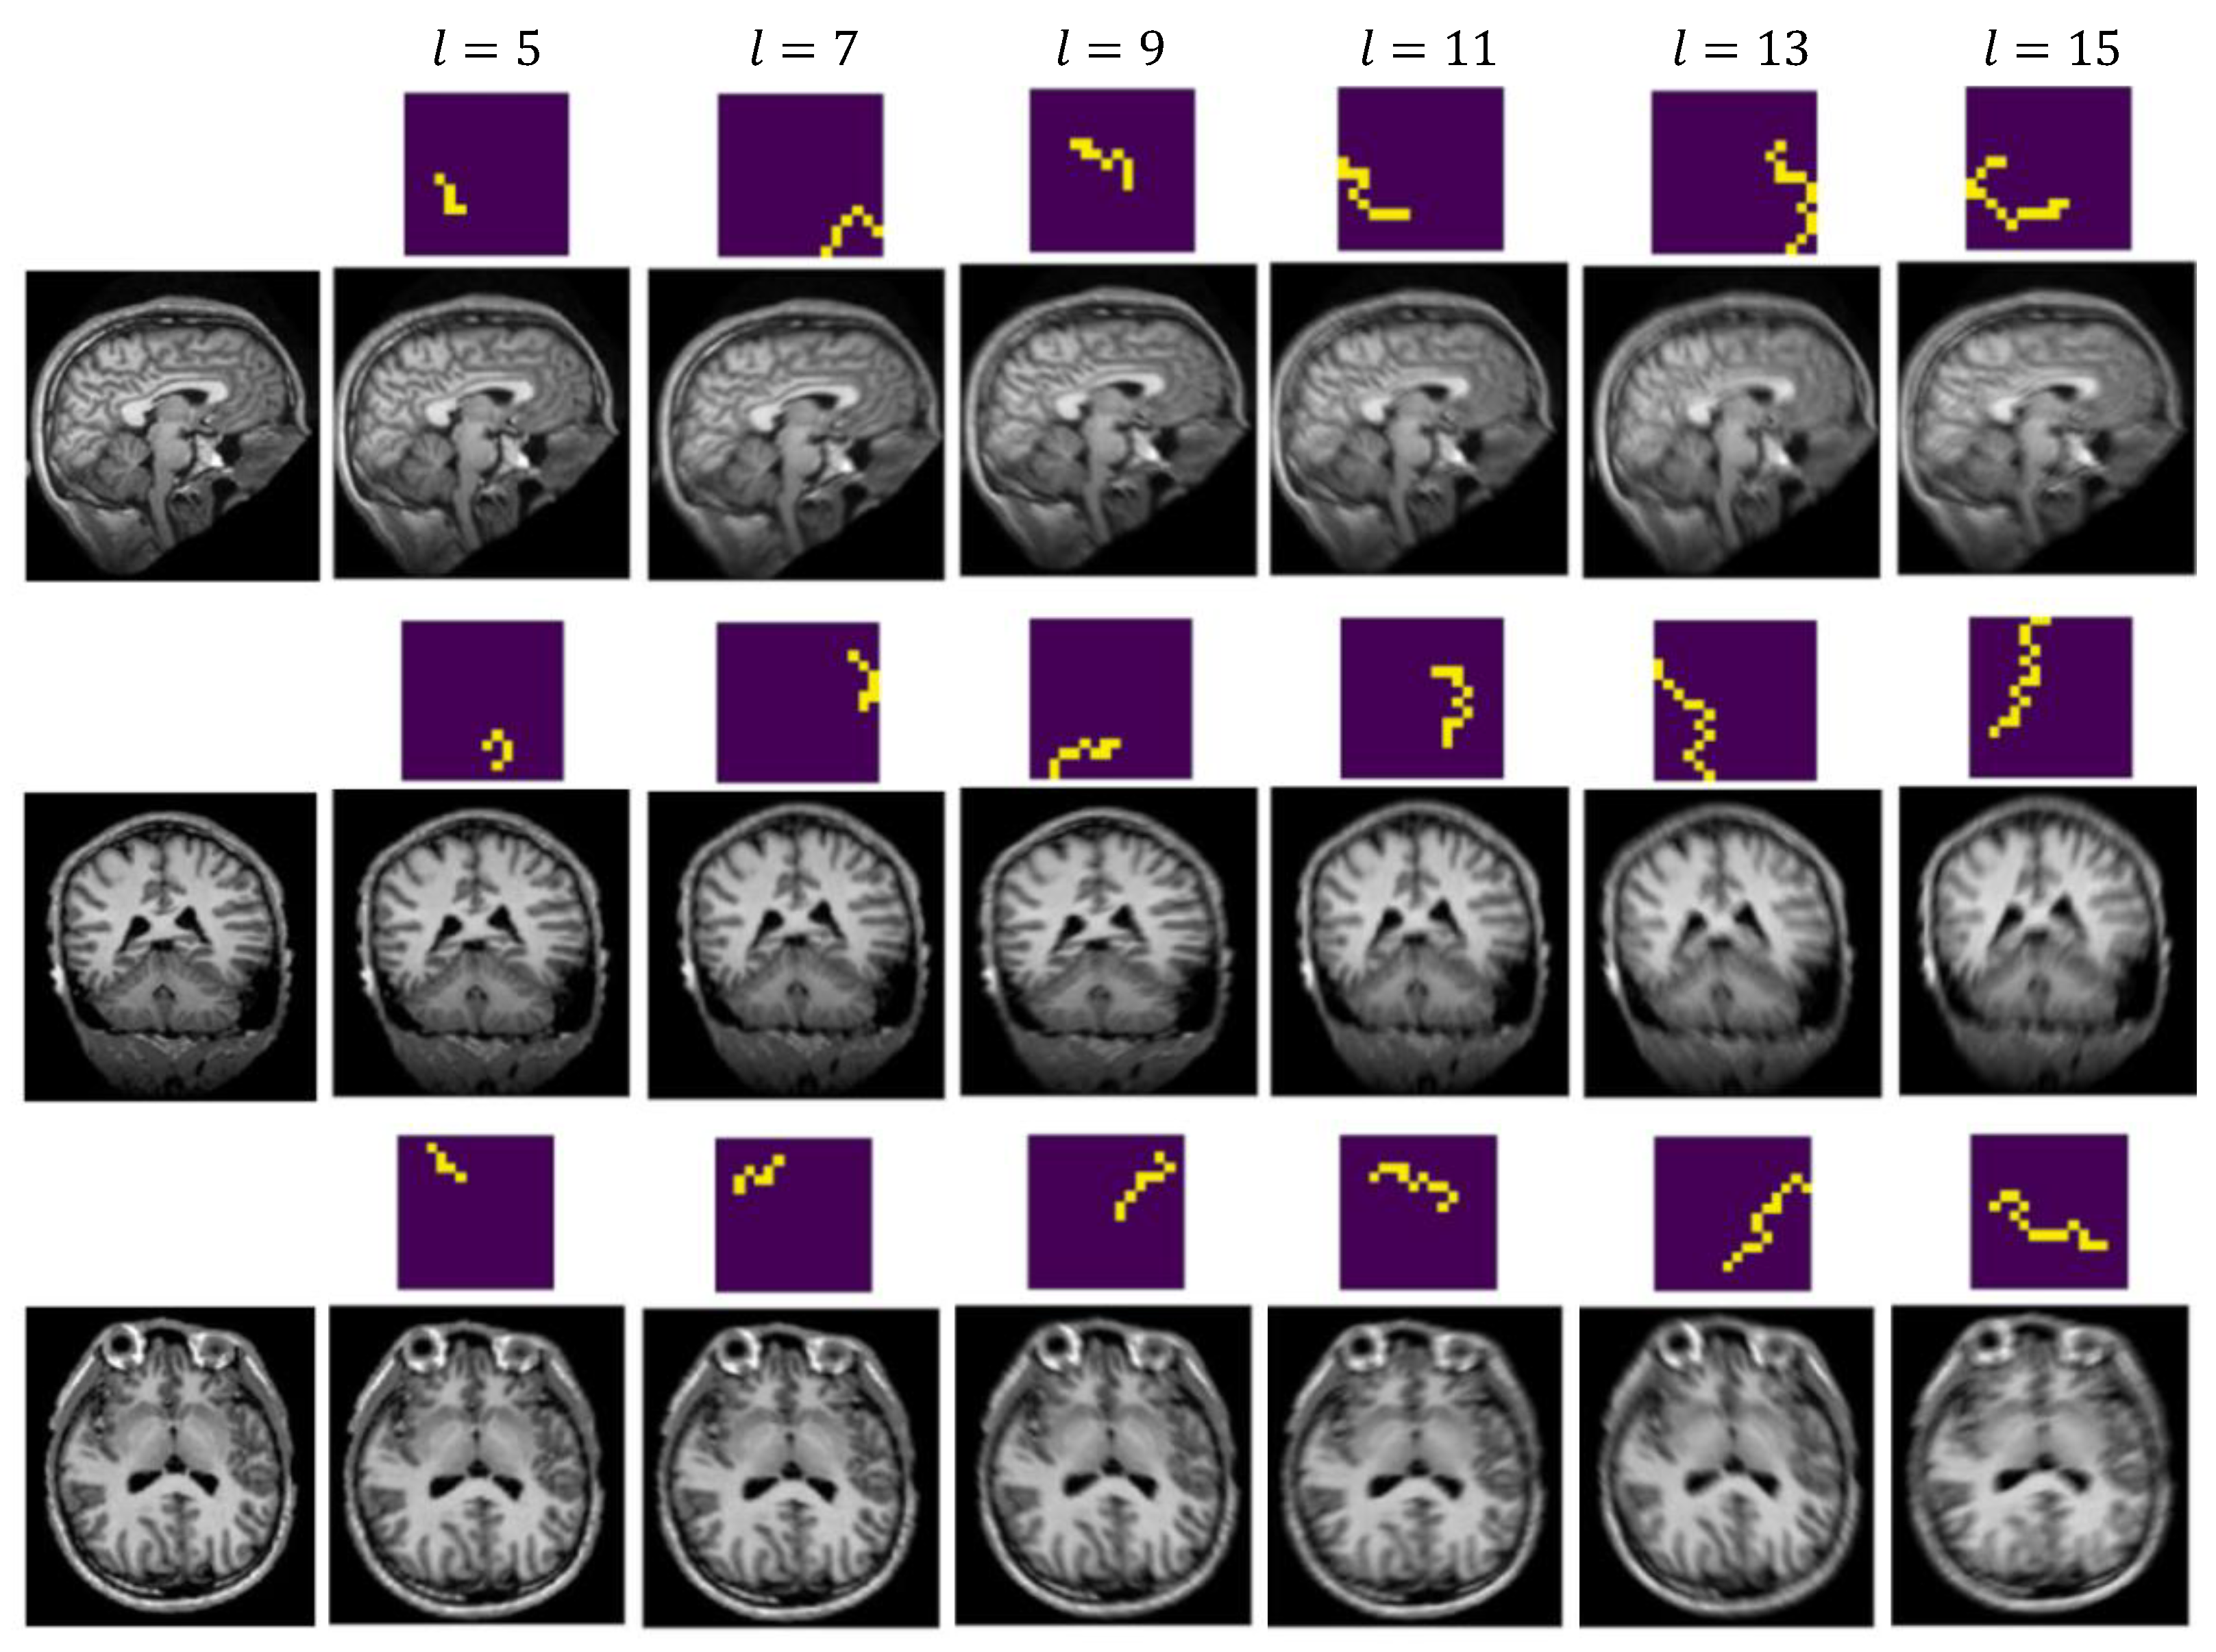

4.2.2. Generate Synthetic Artifact-Affected Data